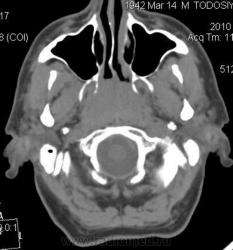

Мужчина 67 лет, обратился к отоларингологу с жалобами на заложенность носа, сосудосуживающие капли - без эффекта. Болен около месяца. На осмотре ЛОР-врач выявил образование свода носоглотки, направил на КТ.

Плотность 37-45 ед.Н, размеры 2х2х2.5 см. Бугристый контур, прилежит к нижнему контуру основной кости с ее деструкцией и прорастанием в основную пазуху. Диагноз не вызвал сомнений, решено контрастирование не выполнять. Направлен в областной онкодиспансер, ждем заключения.

Первые три - первичные аксиальные срезы в "мягкотканном" и "костном" окне в зоне интереса.